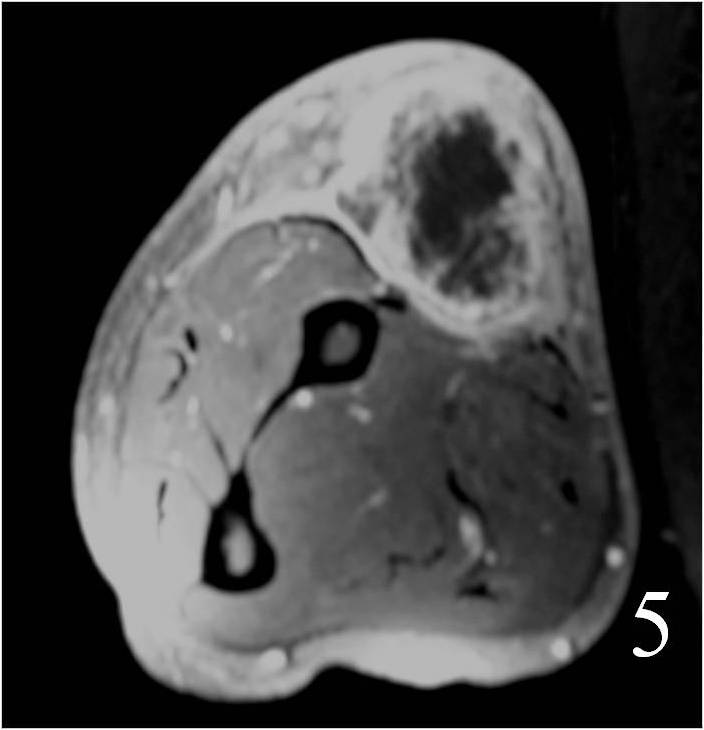

Large heterogeneous mass (Fig. 4, 5, 6)

Fig. 4 MRI of a leiomyosarcoma of the forearm shows a mass isointense to muscle on T1W image, heterogeneous on T2W (Fig. 5) and enhances with contrast T1W fat suppressed (Fig. 6)